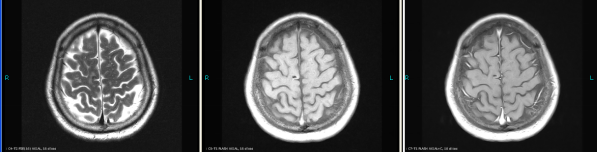

A 66-year old male patient with a smoking history was received by the Outpatient Department on September 14, 2015 due to “coughing for more than one month”. Main symptoms included a dry cough, a small amount of white phlegm, but freedom from fever, chest pains, bloody sputum, and any other discomfort. Stage IV-lung cancer is associated with anorexia and a loss of nearly 10 pounds. The patient had a poor constitution in the past, with a history of “acute hepatitis”, “type-2 diabetes” and “obsolete pulmonary tuberculosis”. The patient was accepted in the Department of Respiratory Medicine on September 15. The results of a lung CT scan indicated a “space occupied for posterior basal segment of right inferior lung and enlarged for mediastinal lymph nodes”. The patient was approved for a CT- guided transthoracic needle biopsy, immunohistochemistry, EGFR gene mutation detection, and systemic metastases assessment. He was diagnosed as “primary lung cancer, right lung adenocarcinoma, T4N3M1B (lung, pleura and brain), and stage-IV EGFR Exon 19 deletion mutation (Fig. 1A and Fig. 2A)”.

The patient checked for further treatment on November 23, 2015. A pre-chemotherapy assessment was made and the results showed multiple bone metastases and multiple enlarged lymph nodes in the left shoulder blade, the fourth lumbar, the right iliac bone and other locations. Performance status (PS) was only one point. Pemetrexed Disodium (500 mg/m2 d1) + Carboplatin (AUC 5 d1) + Bevacizumab (7.5 mg/Kg d1) was administered beginning November 26, 2015 for the chemotherapy treatment and supportive therapy was provided, such as, dehydration, reduction of intracranial pressure, promotion of bone repair, pain relief, and waist protection. After discharge, the coughing basically disappeared and the dizziness, backaches, and hemiparesthesia of the left side were significantly improved. Patient emotional state and sleep quality was significantly improved. It was basically normal after a routine blood examination. A second chemotherapy treatment was successfully completed on December 18 (the program is idem). The patient returned to the hospital on January 6, 2016 and was proposed for a third chemotherapy. The pre-chemotherapy assessment showed that the measurable, targeted right lung lesion had decreased (3.2 mm, with a rate of decrease 44.8 %) (Fig. 1D). Lymphangitis carcinomatosa was significantly decreased and right frontal nodulus lesions were reduced significantly (Fig. 2C). No new lesions were found. Efficacy was assessed as partial relief (PR). A third and fourth chemotherapies were completed on January 9 and January 30, 2016. Efficacy was re-assessed as PR (Fig. 1E) with lung CT review as an outpatient on February 11. Since then, the patient had been subjected to a combined administration program of pemetrexed disodium (500 mg/m2 d1) + bevacizumab (7.5 mg/Kg d1) for continued chemotherapy. A lung CT and a cranial MRI were peformed on April 16. The results showed that the control of lung lesions and intracranial lesions were basically the same as before (Fig.1F and Fig. 2D). The patient had no cough, backaches, or hemiparesthesia and the quality life significantly improved. PS was decreased to zero.